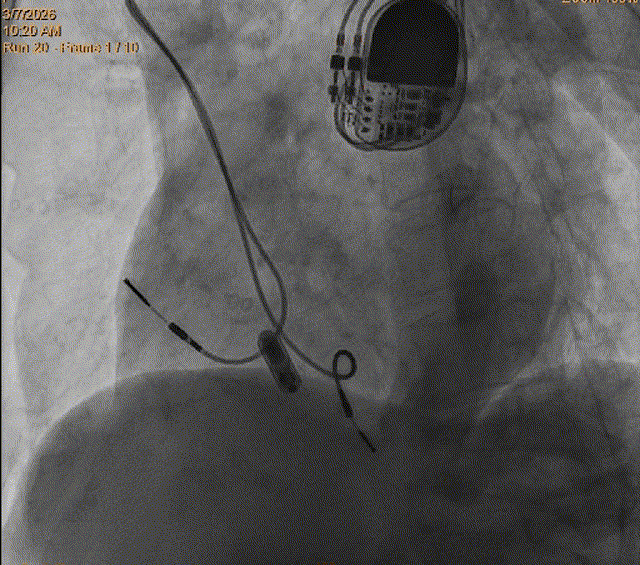

在分析了患者情况和充分考虑患者及其家属意愿后,攀枝花学院附属医院罗晓鸣教授和团队专家们为患者量身定制了缜密的手术方案,采用最新一代Micra AV无导线起搏器进行植入。这款起搏器无需植入电极导线,也无需在胸前皮下制作囊袋,解决了患者担心手术影响外观、感染风险大等忧虑。Micra AV无导线起搏器手术直接植入在心腔内,无伤疤、无切口,患者在植入后几乎感觉不到起搏器的存在,很大程度上提升了患者的治疗体验。

Micra AV无导线起搏器的手术在非全身麻醉下进行,通过股静脉穿刺,将起搏器通过导管植入到心腔内部,手术时间仅有50分钟,患者术后反应良好,预计五天后即可恢复正常的工作和生活。